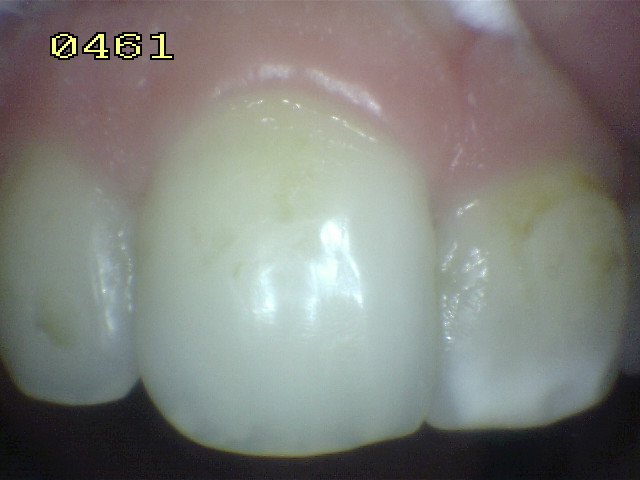

El examen visual debe emprenderse con los dientes completamente secos y con una buena iluminación.  El uso de amplificación de imagen también puede ayudar en el diagnóstico. El uso de una sonda se restringe al levantamiento de placa y detritos de comida.

El diente al lavarse y secarse con la jeringa triple deja expuesto esmalte blanquecino escarchado o opaco que delata un proceso de desmineralización, debido a que el agua se evapora de los microporos. Ver círculos rojos

Una mancha oscura de dentina que se observa a través del esmalte intacto,  adyacente a la fosa y reborde marginal,  indica la presencia de desmineralización. (Imagen 0229)